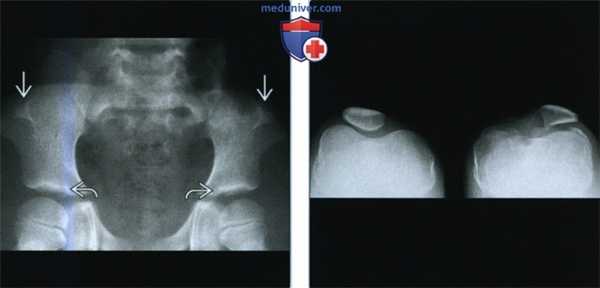

(Слева) Рентгенография таза в ПЗ проекции: визуализируются отдельные «рога» подвздошных костей. Эти рога относительно небольшие. Также обратите внимание на широкие горизонтальные вертлужные впадины, которые визуализируются при большом количестве скелетных дисплазий.

(Справа) При рентгенографии в аксиальной проекции определяются характерные диспластические изменения надколенника. Патологические изменения асимметричные, более выражены в левом коленном суставе. Слева отмечается уплощение латерального мыщелка бедренной кости, а также увеличение медиального мыщелка. Также определяются изменения, характерные для раннего остеоартрита.

• Рога подвздошных костей:

о Симметричные

о Отмечается в 80% случаев

о Проецируются кзади и латерально от центра подвздошной кости

о Пальпируемые

о Бессимптомные

• Отсутствие/гипоплазия надколенника:

о Асимметрично

о Верхнелатеральное смещение

о Колено выглядит уплощенным

о Чрезмерный рост медиального мыщелка бедренной кости

о Гипоплазия латерального мыщелка бедренной кости

о Увеличение бугорка большеберцовой кости